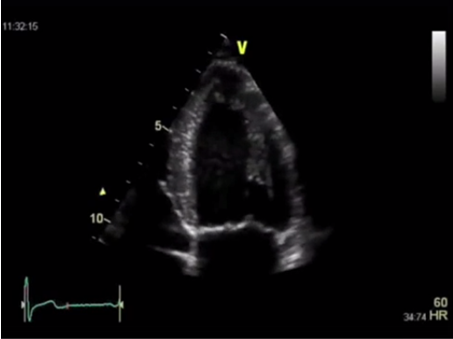

Методы оценки систолической функции левого желудочка:

- измерение ФВ ЛЖ в 2D режиме по Simpson;

- измерение ФВ ЛЖ в 3D режиме;

Методом выбора в оценке систолической функции миокарда является исследование фракций выброса левого желудочка при помощи эхокардиографии. Наилучшими являются измерения при помощи трехмерной эхокардиографии, а используемые иногда измерения в одномерном М-режиме по методу Тейхольца проводить нельзя, в связи с большим количеством неточностей и погрешностей. И при отсутствии трехмерной эхокардиографии исследование выполняется в двухмерном режиме по методу Симпсона.

Измерение ФВ ЛЖ в 2D режиме по Simpson

Измерение ФВ ЛЖ в 3D режиме

И разброс данных, получаемых при трехмерной эхокардиографии, даже у одного врача может составлять около 6%, а при двухмерной – около 10%.

Разница между измерениями в двухмерном и в трехмерном режимах может достигать 23%.

Стоит отметить, что положительной стороной исследования фракции с помощью эхокардиографии является ее доступность. Основные ее ограничения: от качества оборудования зависит качество изображения, имеет значение и опыт врача. Поэтому для серийной оценки фракции выброса левого желудочка необходимо использовать одно и то же оборудование, а измерения, желательно, чтобы выполнял один и тот же врач.